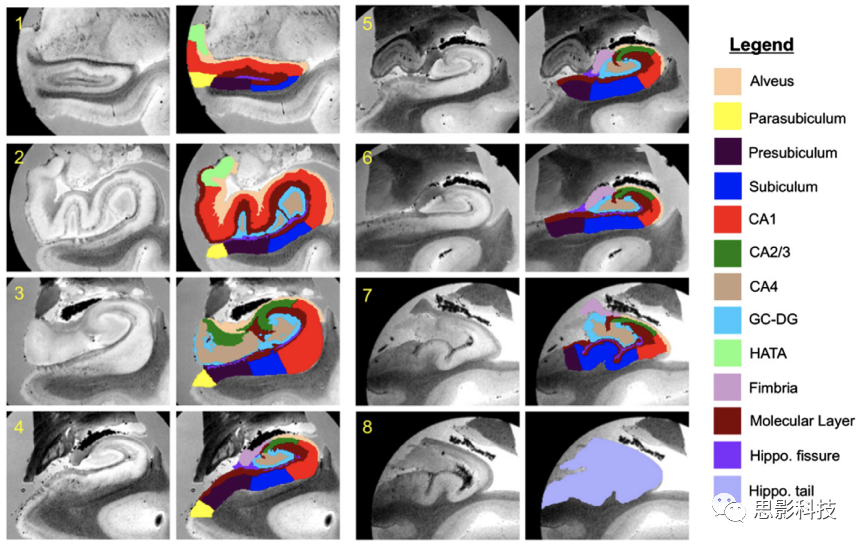

五、皮層下區(qū)域體積分析

尺度更小的分析,如海馬、杏仁核的亞區(qū)分割,如今也可以實現(xiàn)。

1. 海馬亞區(qū)分割與體積分析。主要包括:海馬亞區(qū)的分割;海馬亞區(qū)的體積提?。缓qR亞區(qū)體積的統(tǒng)計檢驗。

圖示.海馬亞區(qū)分割